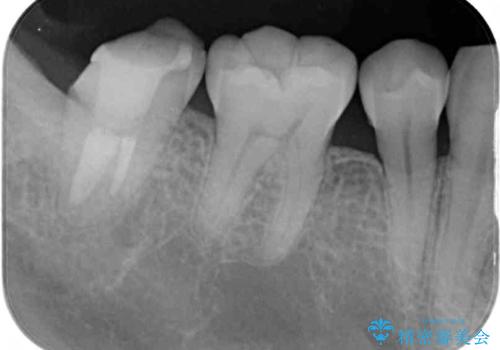

- 根管治療の専門医院で根管治療を行った後、セラミッククラウンによる補綴治療を希望して来院された患者様です。

根管治療後の土台も構築されていたので、仮歯に置き換えた後にフルジルコニアクラウンにて補綴することとしました。